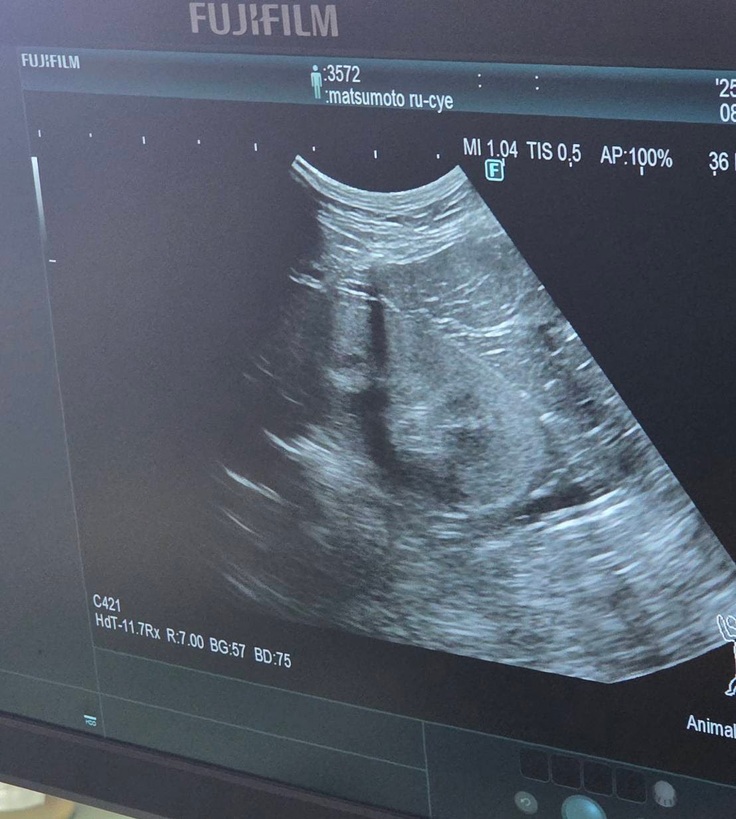

血液検査の写真は撮れなかったのですが、エコー検査では

↓腎臓転移なし

↓肝臓転移なし

↓膀胱転移なし

↓反対側の腎臓も転移なし